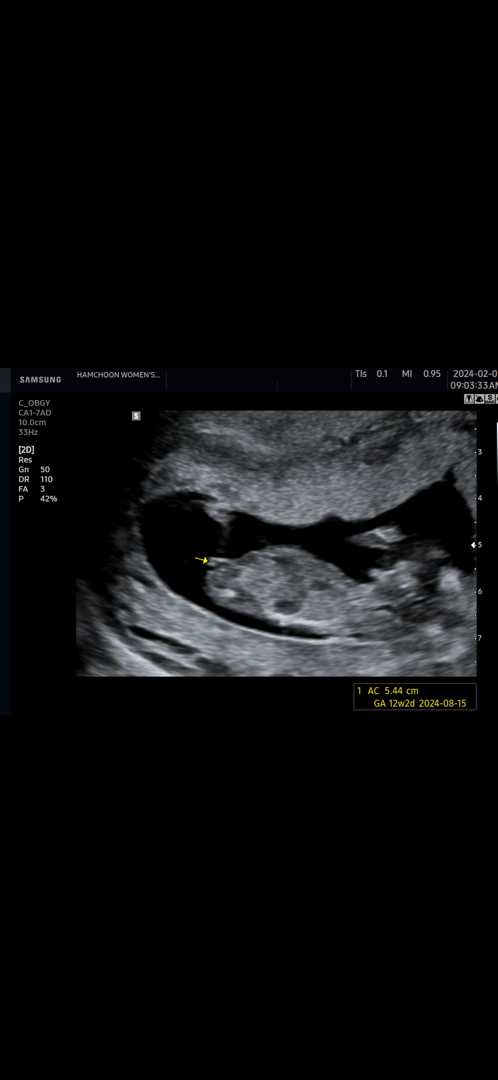

12주 4일 각도법👼🏻🩵

12주차 4일에 찍은 초음파인데 아들일까요 딸일까요ㅎㅎ